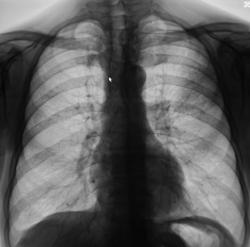

Левосторонняя верхнедолевая сегментарная пневмония? Или?

Пациент направлен врачом терапевтом в рентгеновский кабинет на рентгенографию органов грудной полости с диагнозом "Левостороняя пневмония?". Жалобы вроде - бы типичные.

Произведена рентгенография в стандартных проекциях.

Уважаемые коллеги! Лично я не стал бы спешить категорично высказаться о туберкулезе или о пневмонии. В данном случае имеет место негомогенная довольно слабой интенсивности инфильтрация легочной ткани в проекции S2 и Sax верхней доли левого легкого. Необходимо порекомендовать коллегам терапевтам провести курс неспецифической терапии пневмонии. Через 7-10 дней контроль. Есть положительная динамика - пневмония. Нет - туберкулез.